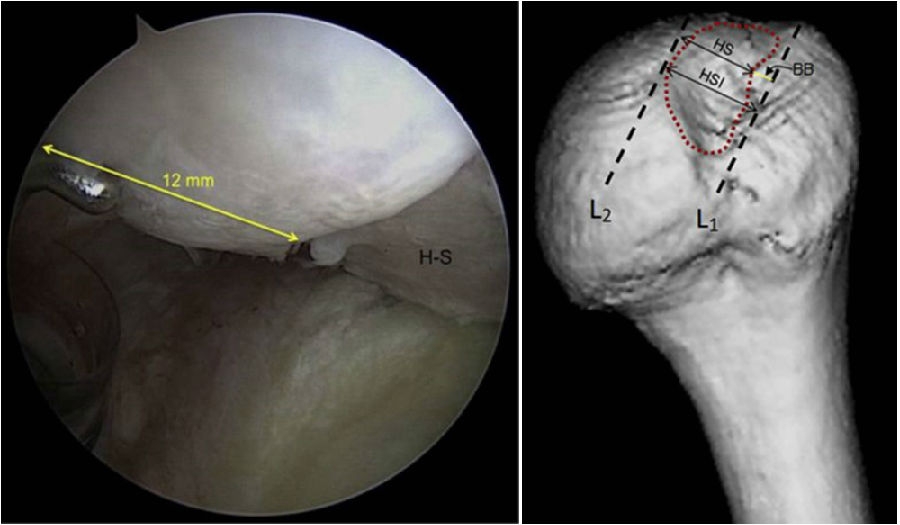

四、肩关节脱位轨迹评估:关节镜下测量评估法

关节镜下肩胛盂轨迹(Glenoid Track,GT)评估是金标准,可以监测一侧骨缺损、Hill-sachs损伤间距评估。

术中通过评估肩胛盂轨迹,可以计算出骨缺损的范围和比例,另外评测肱骨头凹陷区域距离。

图31 D:15X2=30mm,d:15-10=5mm,83%D=24.9mm,d/D=16.7%

根据公式,可以计算出存在骨缺损的肩胛盂轨迹(0.83D-d),此例中的肩胛盂轨迹为0.83×30-5=19.9mm。

图32 Hill-Sachs损伤测量方式

上图为Hill-Sachs损伤的测量方式,采用前端为4mm的探钩,可以看到Hill-Sachs损伤的区域为3个探钩前端的跨度,因此HS为12mm。

评估报告提示:肩胛盂轨迹(Glenoid Track,GT)19.9mm,Hill-Sachs间距(Hill-Sachs Interval,HSI)24mm。

图34 BB=12

骨桥宽度的测量方式,采用前端为4mm宽的探钩测量,发现骨桥宽度正好为3个探钩前端的跨度,应为12mm。

计算Hill-Sachs间距(Hill-Sachs Interval,HIS)。这个间距应为Hill-Sachs损伤的宽度(HS)加上骨桥(Hill-Sachs损伤的外侧缘到肩袖止点)的宽度(BB),HSI:HS+BB=24mm。